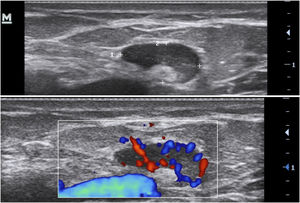

Complementary evaluationsVascularization evaluation with Doppler provides an objective assessment of the degree of inflammation and disease activity. It can be classified as absent, peripheral, internal or mixed (Fig. 10).15,22–24

It is also possible to grade the amount of vascularization23 as high, if there are multiple signs, moderate if there are some signs of flow, minimal if there are a few points and absent. Nodules and abscesses have a peripheral vascularization pattern, simple fistulas, peripheral and mixed, and complex fistulas show a mixed pattern. Nodules show moderate to low amount of vascularization20 and abscesses and fistulas show a high to moderate degree of vascularization.13,23 As the disease becomes chronic, the vascularization changes from peripheral to mixed.23